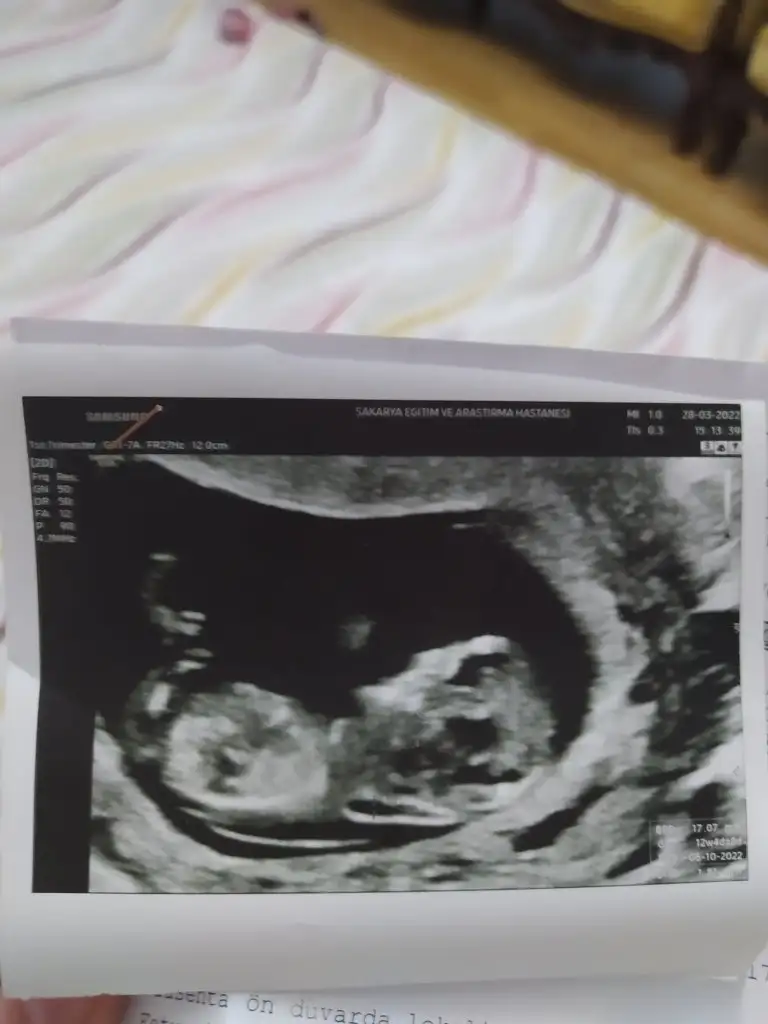

Kızlar 13 haftalık bebeğimin fotoğrafı. Sizce cinsiyeti nedir?